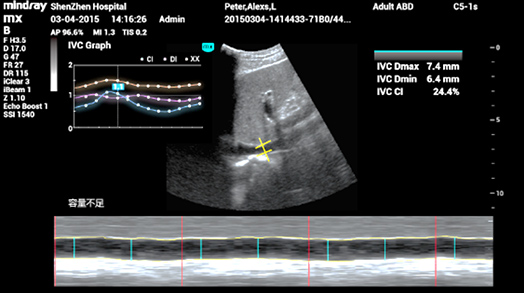

3Smart IVC

Mesure automatique de la Veine Cave InfÃĐrieure (VCI) pour aider à lâÃĐvaluation de la volÃĐmie et guider la gestion des fluides. Un graphique de tendances reprÃĐsentant lâindex de collapsibilitÃĐ ou lâindex de distensibilitÃĐ et la variation de la veine cave infÃĐrieure permet le suivi de lâÃĐvolution des patients en ÃĐtat critique.